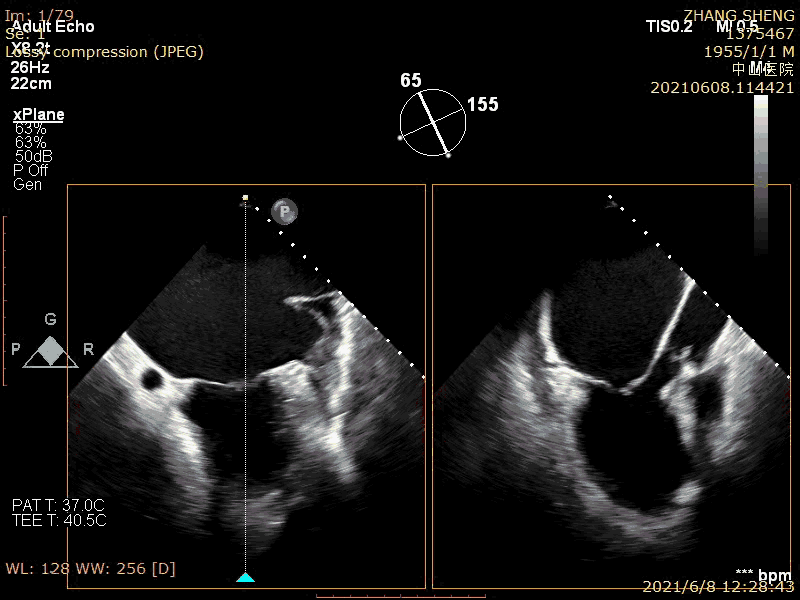

之前,笔者阅读国外文献关于MitraClip解剖入选标准,要求对于FMR的病人,前后瓣尖端之间接合长度要大于2mm。那么问题来了,既然前后瓣叶都接合重叠了,那怎么会出现反流?这个问题解释必须从MR时空滞后角度去分析。 (图10-11),这些患者,由于乳头肌部位心脏收缩减弱,瓣膜被腱索牵拉而不能闭合,出现了收缩早中期的瓣膜闭合延迟而出现MR,而到了收缩晚期,心脏收缩幅度加大,向瓣环靠拢,腱索没受到牵拉而出现了瓣膜闭合和接合。所以,这些患者的MR并非全收缩期,只存在于收缩早中期。左束支传导阻滞患者出现MR主要叶是该机制,因此,通过纠正心脏收缩顺序可以治疗MR。同样,我们中心近期在《European Heart Journal - Case Reports》[3]报道了一组舒张期MR的有趣病例,这些病例甚至二尖瓣的解剖完全正常(图12)。其发生机制也是心脏收缩的时间顺序发生紊乱,导致心室和心房之间的压差逆转或者腱索被提牵拉限制,从而导致MR。

图10  MR发生之时空滞后机制

图11  发生之时空滞后机制